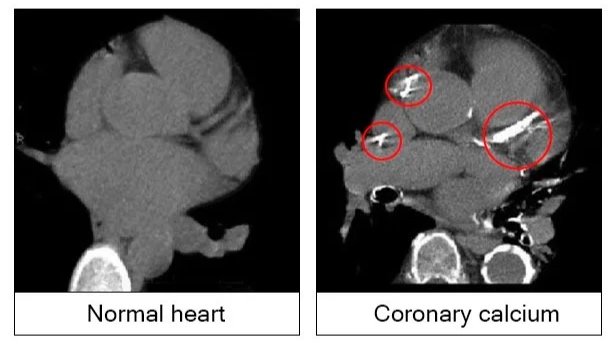

CT Calcium Score

A CT Calcium Score is a noninvasive heart scan that shows calcium deposits in your coronary arteries. Using a CT scan of your heart, radiologists are able to identify calcium in your heart and give you a score, indicating your risk of a heart attack. By detecting risk before symptoms develop, this test helps patients make proactive choices to protect their long-term cardiovascular health. This test is a cost-effective tool to gain further insight into your heart health.